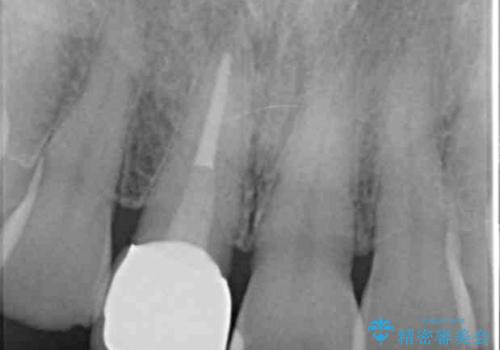

- 十数年前に治療した前歯のクラウンの歯ぐきの位置が変化し、黒いラインが見え審美性の改善を求めて来院されました。

ファイバーコアのやりかえを行ったのち、金属を用いないジルコニアクラウンによる再補綴を行い前歯の審美性の向上を計画します。